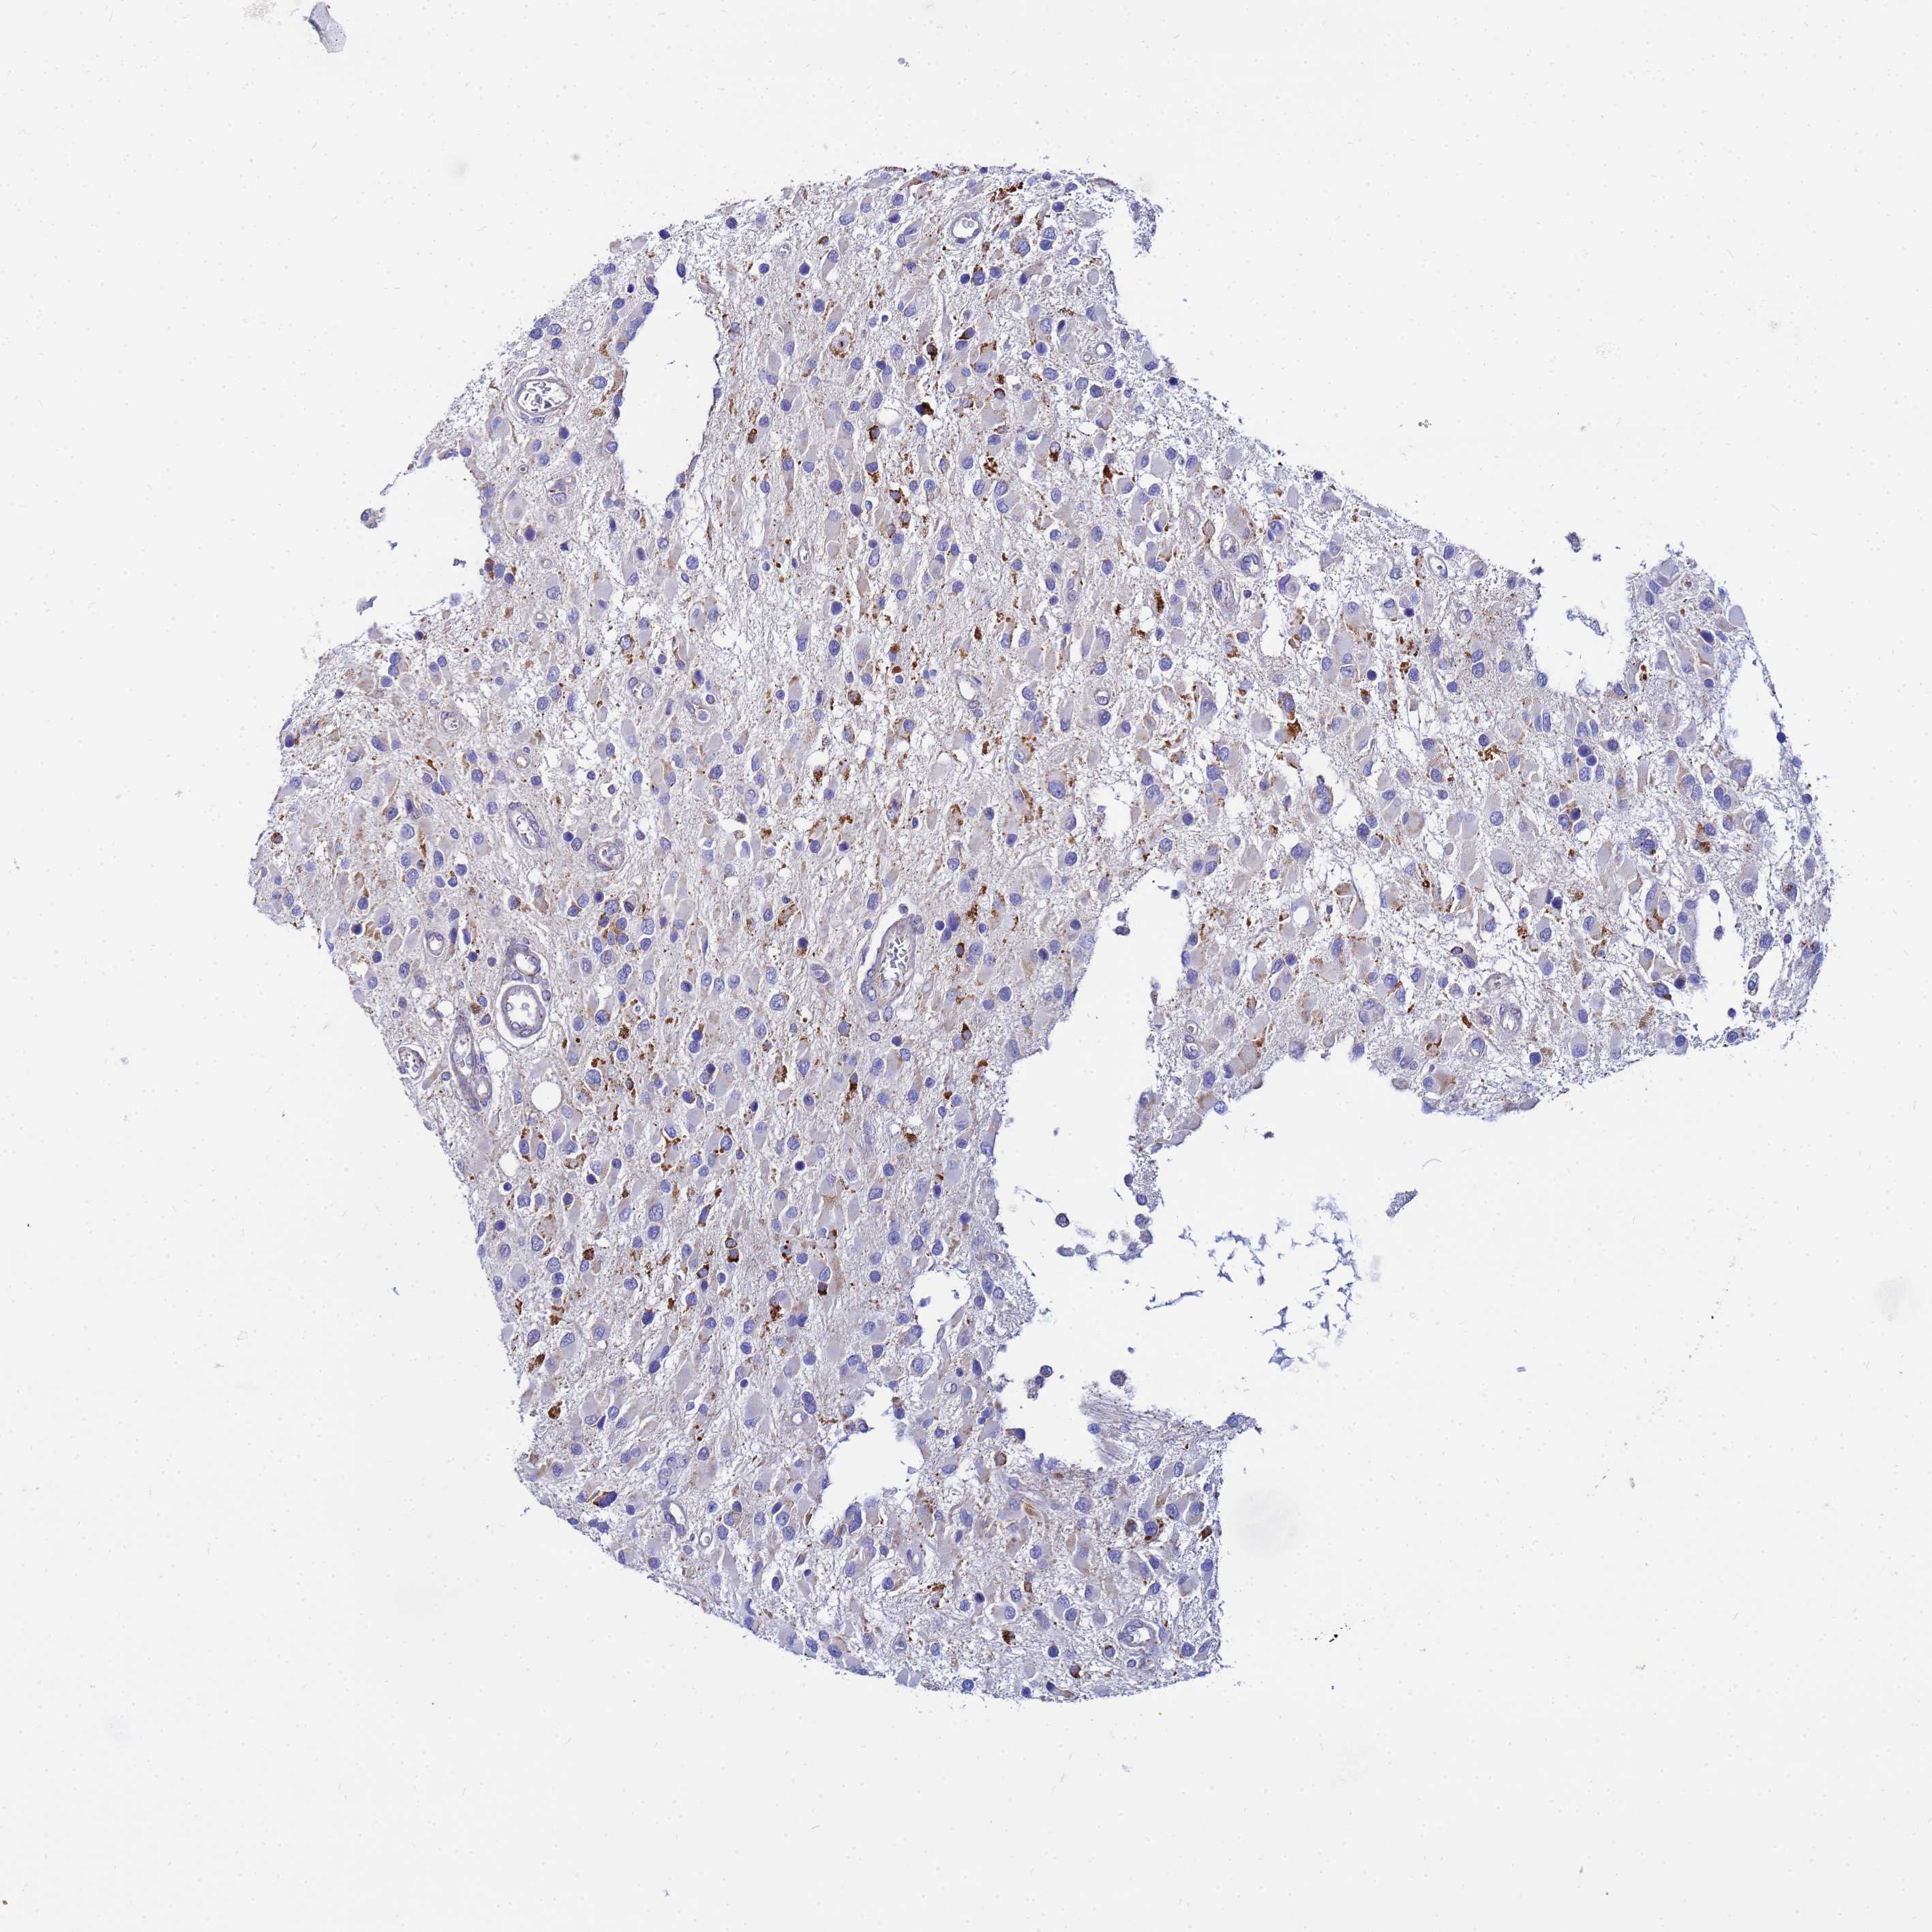

GLIOMA - Protein expressioni

A mouse-over function shows sample information and annotation data. Click on an image to view it in a full screen mode. Samples can be filtered based on level of antibody staining by selecting one or several of the following categories: high, medium, low and not detected. The assay and annotation is described here.

Note that samples used for immunohistochemistry by the Human Protein Atlas do not correspond to samples in the TCGA dataset.

Antibody stainingi

Antibody staining in the annotated cell types in the current human tissue is reported as not detected, low, medium, or high, based on conventional immunohistochemistry profiling in selected tissues. This score is based on the combination of the staining intensity and fraction of stained cells.

Each image is clickable and will lead to virtual microscopy that enables deeper exploration of all samples and also displays staining intensity scores, fraction scores and subcellular localization as well as patient and tissue information for each sample.

Antibody HPA042145

Antibody HPA044987

Antibody CAB045971

Antibody CAB045972

Staining

High

Medium

Low

Not detected

Intensity

Strong

Moderate

Weak

Negative

Quantity

>75%

75%-25%

<25%

None

Location

Nuclear

Cytoplasmic/membranous

Cytoplasmic/membranous,nuclear

Glioma, malignant, Low grade

Glioma, malignant, High grade